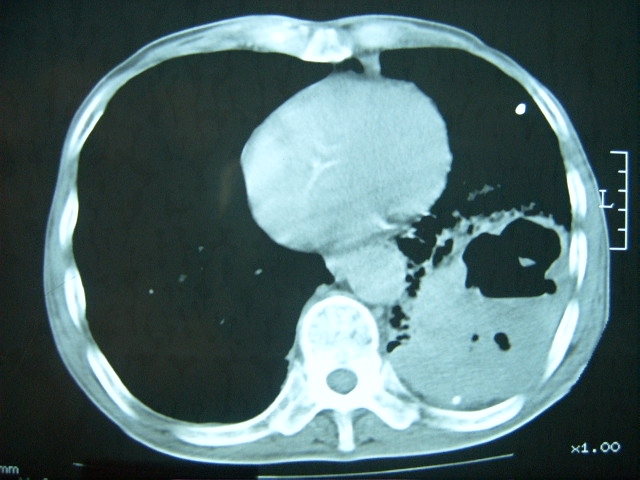

男74岁,咳嗽,寒战,低烧。有糖尿病史。

糖尿病并发肺脓肿建议治疗后复查

考虑:糖尿病合并:1、左下肺炎继发肺脓肿;

考虑:1、左下肺脓肿;不排除霉菌感染

两肺慢性炎症伴脓肿形成,不除外继发霉菌感染。

两肺结核,左下肺大片实变,内见空洞性病变,壁不规则,结合糖尿病史,考虑:结核性?霉菌性?建议结合实验室检查或治疗后复查。